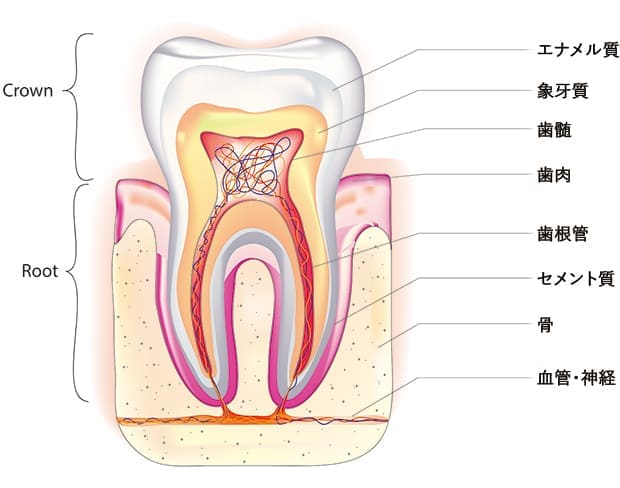

根管治療とは、歯の根にある部分の治療を指します。歯の内部には、「歯髄」と呼ばれる柔らかい組織があり、根管の先端にある小さな孔を通じて、顎の骨の中の神経や血管とつながっています。歯髄が進行した虫歯や外傷によって細菌に感染すると、歯が激しく痛んだり、歯茎が腫れたりすることがあります。こうした症状を改善し、歯を残すためには、感染した歯髄を除去する必要があります。

むし歯が進行して歯の神経(歯髄)に達し、根の先へ感染が広がる過程で、次のような状態が引き起こされます。

- 歯髄炎

歯の神経に炎症が生じ、強い痛みを感じる状態です。 - 歯髄壊死

炎症により歯の神経が死んでしまい、痛みを感じなくなった状態です。 - 根尖病巣・根尖性歯周炎

根の先に炎症を起こし、骨を溶かして膿が溜まった状態です。炎症が強く起こっている時期(急性期)と静まっている時期(慢性期)があります。

このような場合、細菌に感染した神経や血管、歯質を除去し、きれいに消毒した上で、薬剤を用いて密閉する根管治療を行います。